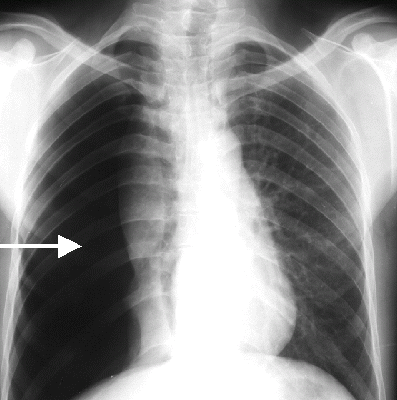

Chẩn đoán Pulmonary Edema, Tràn dịch trong phổi hay Phù phổi là Hỏi bệnh sử và khám thực thể. Chụp X-quang phát hiện thấy các chất dịch trong phổi. Các xét nghiệm khác có thể bao gồm xét nghiệm máu hoặc siêu âm tim để xác định nguyên nhân. Xét nghiệm công thức máu toàn bộ (CBC), bảng chuyển hóa toàn diện (CMP), điện tâm đồ (EKG), Troponin, phân tích nước tiểu (UA). Khí máu động mạch (ABG), siêu âm tim, xét nghiệm đo nồng độ Natriuretic Peptide loại B (BNP).

Click vào ảnh để xem 4 hình ảnh minh họa